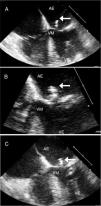

Achados clínicosO ETT revelou achados compatíveis com cardiopatia hipertensiva (dilatação da aurícula esquerda, hipertrofia ventricular esquerda de grau moderado, insuficiência mitral de grau ligeiro e disfunção diastólica grau II) com função sistólica biventricular preservada, e identificou uma massa móvel, apensa aos folhetos da válvula mitral, que o ecocardiograma transesofágico (ETE) confirmou tratar‐se de uma vegetação com 19 x 4mm, aderente à face auricular do folheto posterior da válvula mitral, com grande mobilidade (Figura 1A e B).

Ecocardiograma transesofágico de endocardite trombótica não bacteriana. A e B) ETE inicial com vegetação no folheto posterior da válvula mitral (seta); C) Após curso de antibioterapia empírica, identificando‐se manutenção da vegetação no folheto posterior da válvula mitral (seta) e aparecimento de nova vegetação com cerca de 10mm apensa a corda tendinosa que se dirige ao folheto posterior (asterisco).

AD ‐ aurícula direita; AE ‐ aurícula esquerda; VD ‐ ventrículo direito; VE ‐ ventrículo esquerdo; VM ‐ válvula mitral.

Após quatro semanas de antibioterapia com ceftriaxone, foi repetido ETE que mantinha a vegetação anteriormente descrita e revelou outra vegetação, com cerca de 10mm apensa a uma corda tendinosa que se dirigia ao folheto posterior (Figura 1C).